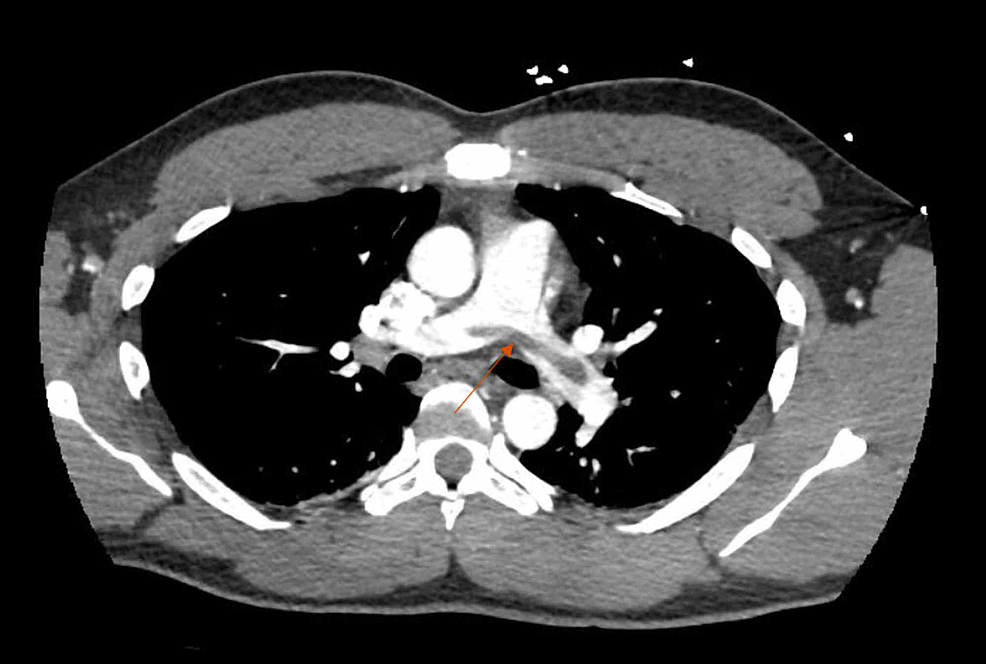

e A CT pulmonary angiogram demonstrating thrombi in right and left Pulmonary Thrombectomy Anesthesia This section provides a comprehensive procedural report for pulmonary artery thrombectomy and thrombolysis. The purpose of this narrative review is to provide guidance to anesthesiologists for the assessment and management of patients having catheter. Surgery puts patients at increased risk for pulmonary embolism (pe). This operation leads to major clinical improvement and is a potential cure for a large majority. Pulmonary Thrombectomy Anesthesia.